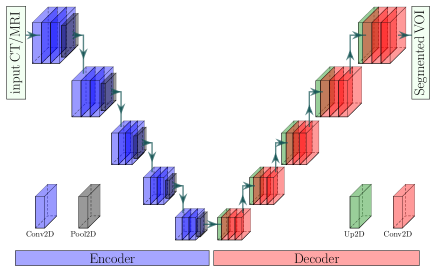

Segmentation of medical image has attained enormous progress notably since after the proposing of UNet [31]. Currently, CNN-based networks have been extensively practiced for the medical imaging domain, exceeding conventional image analysis techniques relying on hand-crafted features [53]. However, the CNN-based network for segmentation incorporates two fundamental elements: the encoder and the decoder [31]. An encoder consists of convolutional and pooling layers. The convolutional layers produce feature maps, whereas the pooling layers continuously decrease these feature maps’ dimension to gain more critical features with more eminent spatial invariance [17]. The decreased resolution feature maps also enlarge the maps’ field-of-view and diminish the computational expense [54]. The decoder projects the distinctive lower resolution features discovered by the encoder onto the higher resolution pixel space to achieve a compact pixel-wise labeling [55]. However, the simple encoder-decoder network, named EDNet, in our implementation is depicted in Fig 4.

The encoder in EDNet is a VGG-16 [56] with the pre-trained weight on ImageNet [57], which has five Convolutional Blocks (CB) and thirteen convolutional layers. Each CB’s output is an input to the next CB through a pooling layer with a stride of . Hence, the encoder’s output feature map has a resolution of for an input resolution of . However, the decoder has five blocks to obtain the input resolutions of the output WHS masks (), where we apply 2D upsampling, with a stride of , convolution with a kernel of , and a batch normalization [58] in each decoder block.

However, the decreased feature maps due to pooling undergo spatial knowledge elimination injecting roughness, poor border knowledge, checkerboard artifacts, over-, and under-segmentation in the segmented substructures [17, 54, 31, 59]. To overcome these problems, the authors in [31] introduced skip connections in a UNet, permitting the decoder to retrieve the associated features discovered at all encoder steps that were missed due to subsampling in the encoder. The feature maps from the encoder’s antecedent layers are concatenated with the decoder’s identical scale through the appliance of skip connections. Applying the skip connection of the popular UNet, we propose a VGG-UNet, where we have also employed the VGG-16 network as an encoder, as shown in Fig. 5.

In our VGG-UNet, we apply the skip connections holding ladder-like compositions [60] motivated by UNet to succeed in the pooling weaknesses. All pooled layers of our network are concatenated channel-wise to a deconvoluted feature map with identical dimensions, where it acts as an offsetting link for the spatial knowledge dropped due to subsampling in the encoder.

Again, the authors in [54] combined features at varied coarseness levels of the encoder in their popular FCN to polish the output segmented VOIs. In this article, we propose a VGG-FCN, as shown in Fig. 6, with the pre-trained VGG-16 network in the encoder. The output feature map of such an encoder has -times fewer resolutions as VGG-16 has five pooling layers.

The employment of upsampling can output the segmented mask with the same size as the input image, called FCN32s. Such an upsampling produces a coarse or rough mask as it utilizes only global information from the more in-depth high-level features. The in-depth features are achieved while operating deeper, which causes the spatial location information lost. That indicates that output from shallower layers has more location knowledge. If we combine both local and global information, it can enhance the segmentation result. The output from the fifth pooling of VGG-16 is upsampled and fused with the fourth pooling in our network. Then, the combined map is upsampled and again linked with third pooling. Finally, we perform upsampling, which provides a segmented WHS mask. Hence, the proposed VGG-FCN is also named VGG-FCN8s, where we use both the local and global information to obtain the final mask.